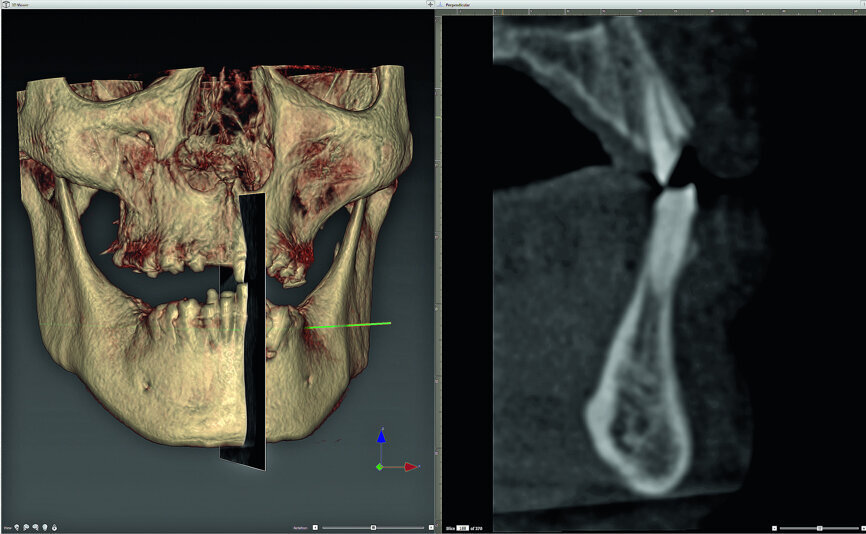

Figure 1 represents a beautifully rendered 3-D maxilla and mandible with the cross-sectional imaging showing the existing teeth and roots in both arches as processed within the interactive treatment planning software (NobelClinician, Nobel Biocare). This vital information allows for a complete understanding that each patient's anatomy is individual and unique and that each patient’s bony anatomy, root positions within the bone, and tooth trajectories may not coincide with the alveolar process. Therefore, without this information, the placement of implants may be compromised, resulting in complications. Therefore, it is imperative that clinicians utilise the most up-to-date 3-D CBCT imaging and interactive treatment planning software to fully appreciate the individual nature of each patient’s unique anatomy.

Fig. 1: Three-dimensional volumetric rendering of the maxilla-mandibular relationship (r), and a sagittal section (l) of this region of interest.